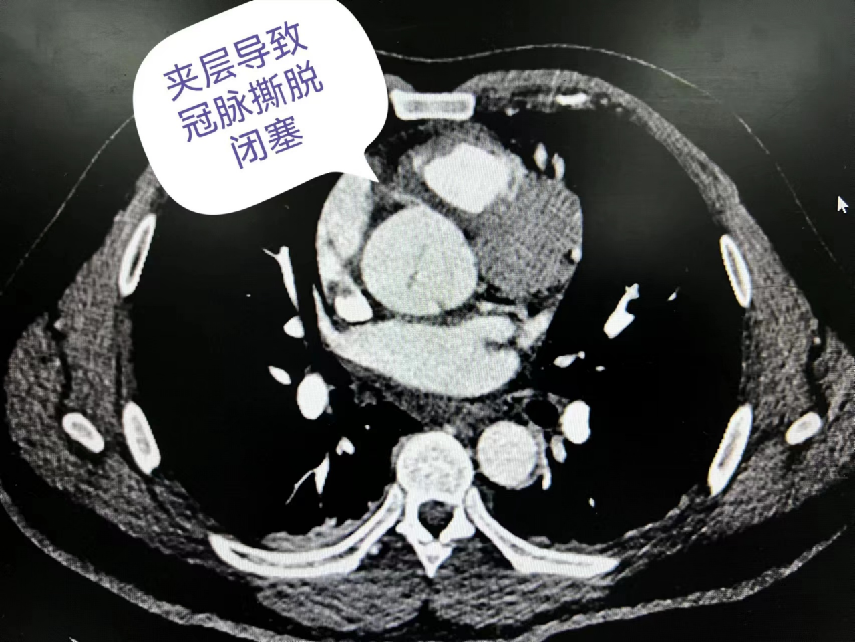

54岁男性,术前血压低,肌钙蛋白升高至44ng/ml,肌红蛋白、BNP指标异常,夹层导致冠脉撕脱闭塞,右心功能衰竭。在ECMO辅助下恢复良好,术后7天撤除ECMO,9天拔除气管插管,术后31天出院。